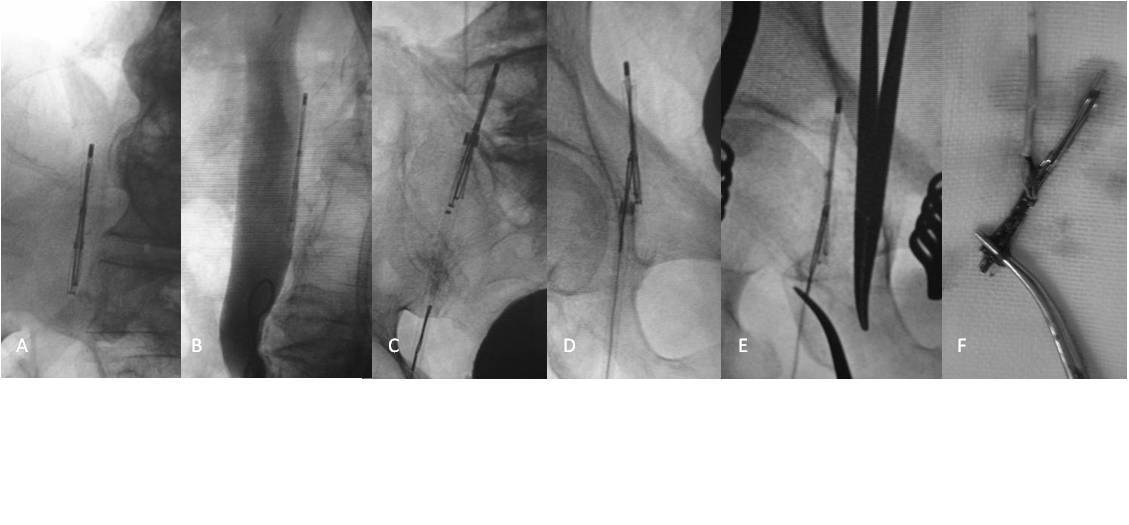

疑难性下腔静脉滤器取出的技巧及策略 - 好大夫

1165x440 - 53KB - JPEG